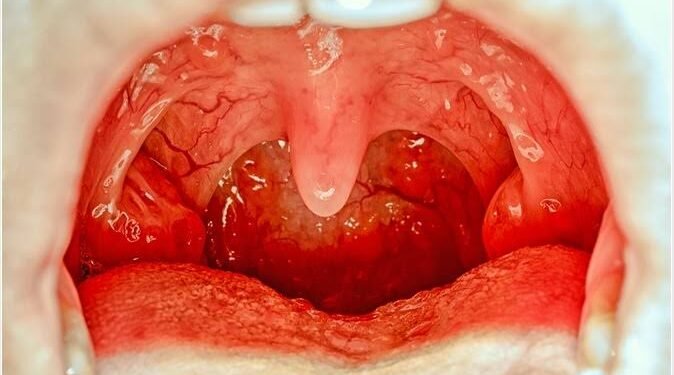

Tonsils are small, oval-shaped tissue in the back of the throat. They serve as the first line of defense in our immune system, helping to fight off viral and bacterial infections that enter through the mouth. But sometimes, they can become more of a liability than an asset, becoming repeatedly infected, a condition known as tonsillitis. In such cases, removal of tonsils, or a tonsillectomy, might be recommended by healthcare professionals.

If the tonsils do regrow, they might appear as bumps in the area where the tonsils once resided. It is also possible that these ‘new’ tonsils can get infected and swell up, much like the ‘old’ tonsils. However, a sore throat or infection isn’t necessarily an indication of tonsil regrowth.